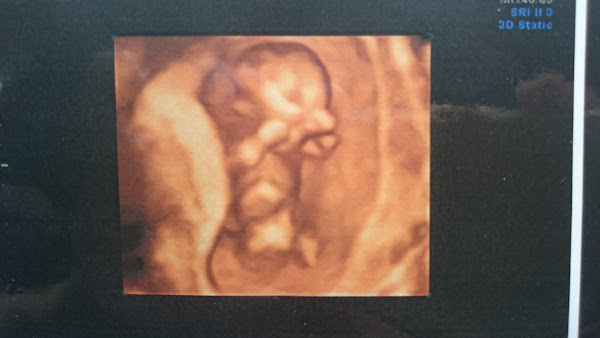

【懷孕】第1-9週記事(孕吐孕吐孕吐)